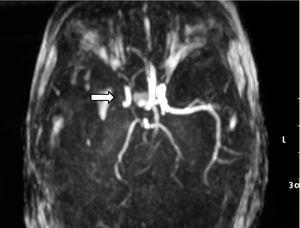

Ante los hallazgos clínicos, a los 3 días de vida se realiza resonancia magnética (RM) cerebral, apreciándose un extenso infarto agudo dependiente de la arteria cerebral media derecha (fig. 1). El EEG y la ecografía cerebral realizadas a los 5 días, mostraron, respectivamente, presencia de ondas agudas frontales derechas ocasionales y un aumento de ecogenicidad en la región parietal, temporal derecha y tálamo derecho. Se completó el estudio con una ecografía Doppler cerebral y una angio-RM (fig. 2) que objetivaron ausencia de flujo en arteria cerebral media derecha confirmando el diagnóstico de infarto cerebral.

Figura 2. Angio-RM: ausencia de ACM derecha.